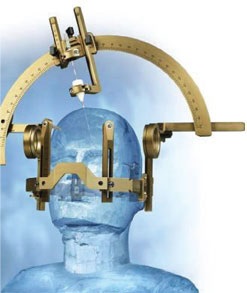

Abordare specială biopsii

Calculele Stereotactica sunt realizate folosind cadre.